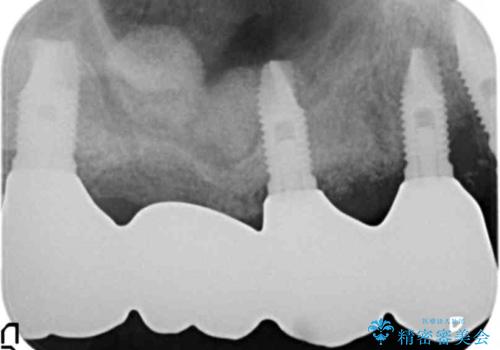

禁煙指導と歯周病治療後、右上臼歯部のソケットリフト及びインプラント治療(右上7654埋入)を行いました。

右上6欠損部の骨が極端に薄くアバットメント装着後に動揺が出たため、右上6フィクスチャーは除去しております。

- ¥1,452,000 (ソケットリフト、インプラント×3本、土台×3本、仮歯×4本、クラウン×4本) ※税込費用は治療当時の料金となります

インプラントの種類:スプラインツイスト(HAコーティング)

固定様式:スクリュー固定